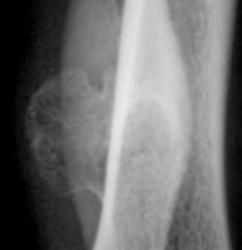

Уважаемые коллеги! Ниже представлено изображение - "Наблюдение Ola-la"

Просьба высказать мнение по поводу "патологического процесса".

Предполагаемые ответы.

1. Костный экзостоз.

2. Костно-хрящевой экзостоз.

3. Остеома.

4. Хондрома.

хрящевой экзостоз

2. Костно-хрящевой экзостоз.

Валентин Львович! Это можно отнести к теме, представленной Вами и Татьяной Валентиновной. Локализация костно-хрящевых экзостозов весьма вариабельна.

1. Костный экзостоз, т.к. не видно хрящевой ткани.

хрящ, как известно, нерентгенконтрастен

частая локализация?

не редкая